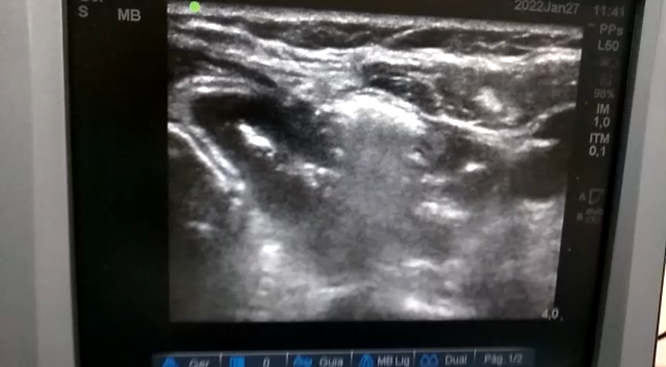

A radioablação é uma técnica em que é feita a ablação do nódulo da tireoide por radiofrequência, com uma agulha que aquece e destrói o nódulo gradativamente.

Neste método, o nódulo é “exterminado” garantindo total funcionalidade da glândula. Esse é um dos grandes benefícios desta técnica em relação à cirurgia de remoção da tireoide, em que o paciente precisa repor o hormônio produzido por meio de medicamentos.

Na tireoide, o maior benefício é remover o nódulo pelas ondas de radiofrequência sem remover a glândula da tireoide. E para o paciente, os benefícios são imensos já que não existe corte nem cicatriz e que as funções hormonais são preservadas, a anestesia é local, o Paciente fica cerca de três a quatro horas internado, não é entubado. Dentre as principais vantagens, temos a que o Paciente, mesmo sendo câncer, não precisa tomar o hormônio da tireoide, evitando a reposição sintética. Portanto uma vantagem é que na ablação os pacientes não precisam tomar hormônios após o tratamento! É preciso entender o critério de cada caso para saber se a radioblação é indicada ou não.